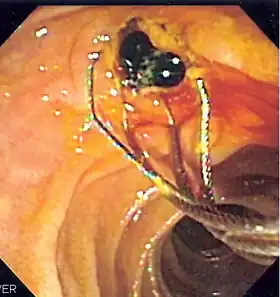

![]() Duodenoscopic image of two pigment stones extracted from common bile duct after sphincterotomy | |